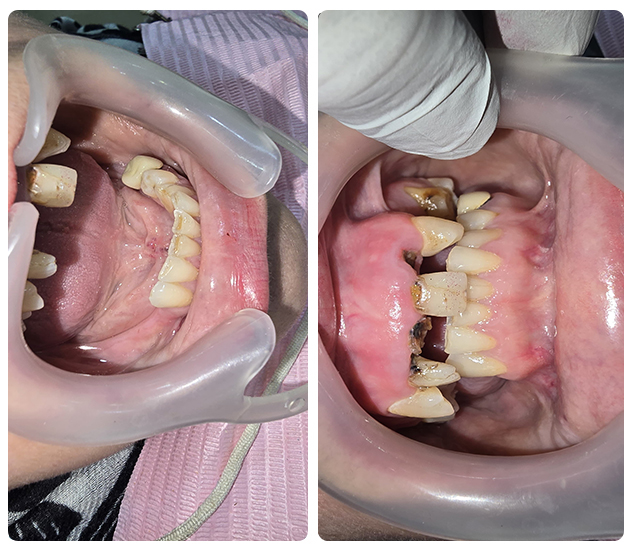

Full Mouth Zirconia (All-Ceramics)

Case 1